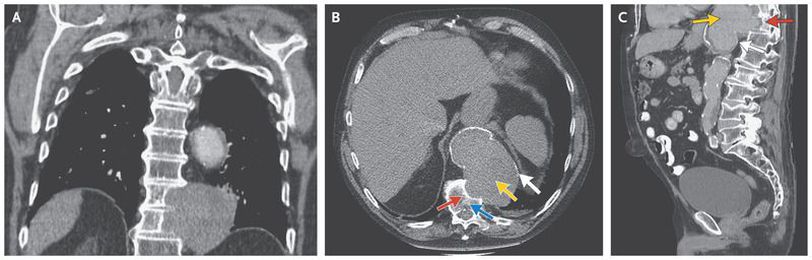

A 74-year-old man presented with acute back pain but without neurologic symptoms. The blood pressure was normal. He had a history of hypertension, open repair of an aortic infrarenal aneurysm, and end-stage renal failure that required hemodialysis. Computed tomography revealed a thoracic aneurysm that measured 8.1 cm by 11.7 cm in the greatest dimensions on the axial view and well-corticated erosions of thoracic vertebrae 10 and 11 (Panel A shows the coronal view, Panel B the axial view, and Panel C the sagittal view; yellow arrows show the aneurysm, red arrows the erosion, and the blue arrow thoracic vertebra 11). Thoracic vertebral erosion, which is more often seen after aortic graft surgery, is a rare complication of thoracic aortic aneurysm. The suggested mechanism is repetitive mechanical pressure causing relative ischemia in the bone, which leads to lysis and bone destruction. Differential considerations for a retroperitoneal mass eroding vertebrae include tumor and infection. The preservation of disk spaces seen in this patient makes infection unlikely, and the presence of a thin calcific rim surrounding the mass (Panels B and C, white arrows) is most consistent with a large aortic aneurysm. Because of the patient’s poor general health, no surgical repair was performed. With conservative treatment, the patient lived another 3 years. He died after a short episode of recurrent back pain for which palliative treatment was given.